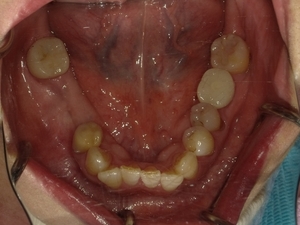

ガタガタとした歯並びや八重歯(叢生)CASE75